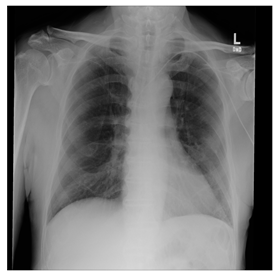

Breast-MRI-NACT-Pilot is an MRI-type image database, collecting breast medical images of 64 patients. Some samples are shown in Figure 12a.

Figure 12.

Sampled images in the tested benchmark databases: (a) Breast-MRI-NACT-Pilot (breast), (b) ACRIN-DSC-MR-Brain (brain), (c) NIH (chest), (d) Lung-PET-CT-Dx (lung), (e) Prostate-MRI (prostate), and (f) Other grayscale standard images.

ANIH is an X-ray type image database collecting chest medical images. Some samples are shown in Figure 12c.